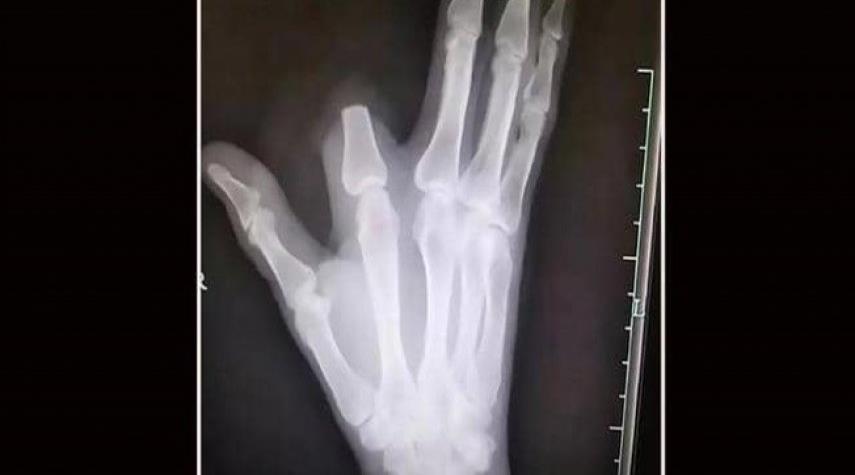

قطع إصبعه بسبب لدغة أفعى..ثم اكتشف "المفاجأة الصاعقة"